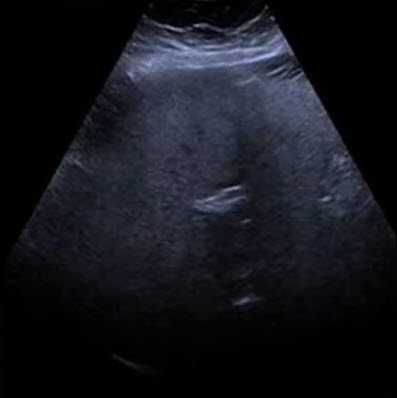

Как выглядит доля Риделя на УЗИ печени